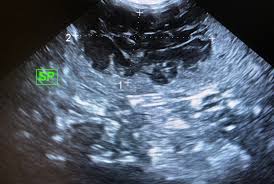

Liver Cancer In Dogs Symptoms Treatment And Life Expectancy Petmd from www.petmd.com Symptoms of hemangiosarcoma in dogs. The technical name for this is the symptoms of hemangiosarcoma. Spontaneous hemangiosarcoma in dogs has notable predilection sites, with common locations for primary tumors being the spleen, right atrium and auricle (figure 45), liver, and skin. Hemangiosarcoma is a malignant cancer of the blood vessels in dogs. Types of hemangiosarcoma in dogs. Treatment of hemangiosarcoma in dogs. Hemangiosarcoma (hsa) is an aggressive, malignant cancer of the cells that line blood vessels most commonly presents as a mass on the spleen, but may also appear on the liver. Hemangiosarcoma symptoms include breathing difficulties, lethargy, abdominal swelling, pale gums, exercise intolerance, rapid heartbeat, appetite and weight loss, lameness hemorrhaging is possible.

This form of hemangiosarcoma is the easiest to surgically remove and has the greatest chance of cure if it is caught before the cancer has spread. The symptoms can be life threatening. Spontaneous hemangiosarcoma in dogs has notable predilection sites, with common locations for primary tumors being the spleen, right atrium and auricle (figure 45), liver, and skin. 5 hemangiosarcoma in dogs symptoms. Hemangiosarcoma causes different symptoms in dogs based on where the tumor is located.